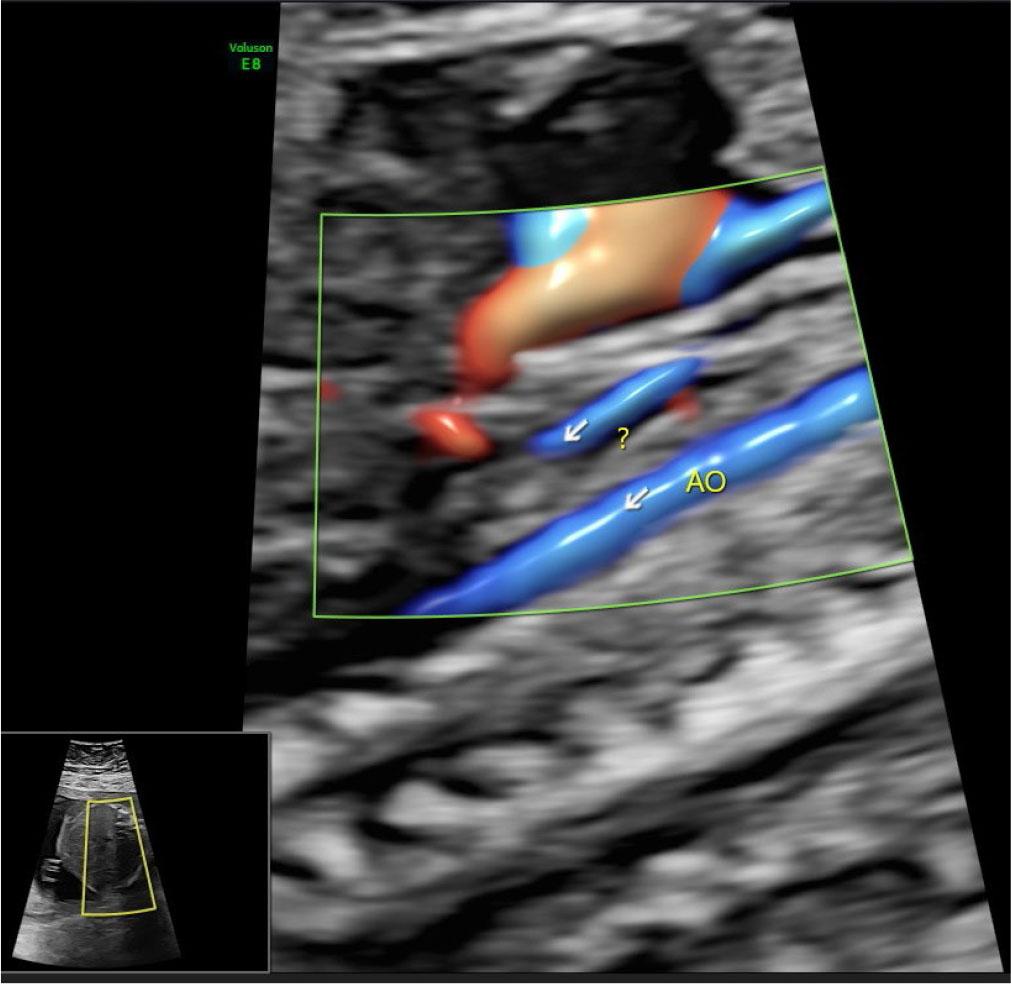

| AO [mm] | 2.6 | 3.3 | 3.3 |